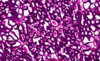

מה בסלייד?

corpus leteum

מה תפקידו של הגופיף הצהוב (הזקיק שנשאר בשחלה לאחר שהביצית יוצאת) במהלך ההריון?

תומך בזמן ההיריון, מפריש אסטרוגן ופרוגסטרון, בערך 5 חודשים לתוך ההריון

אם אין הריון הוא מתנווץ ונהיה גופיף לבן- רקמת צלקת.

מה קורה בכל ביוץ שאין בו הריון?

מגיעים פיברובלסטים ומאקרופאגים שאוכלים את התאים, הפיברובלסטים מפרישים קולגן שיוצר רקמת צלקת- גופיף לבן.

כל ביוץ ללא הריון משאיר צלקת.